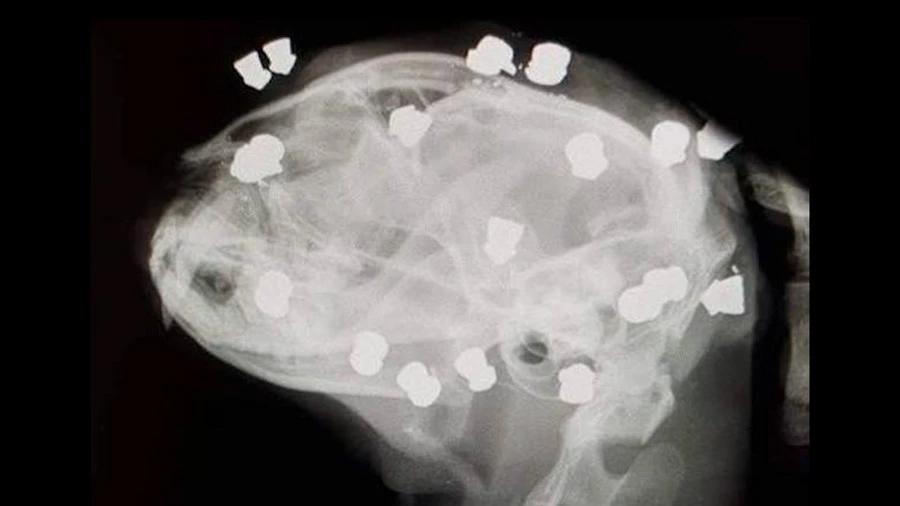

Có 18 viên đạn ở vùng đầu của chú mèo. Ảnh: RT

Một người đi đường đã nhìn thấy chú mèo trong tình trạng bê bết máu đi loạng choạng trên đường và nhanh chóng đem chú mèo tội nghiệp tới bác sĩ thú y. Và họ đã tìm thấy 18 viên đạn nhỏ cắm vào mặt, đầu và cổ chú mèo.

Loại đạn được tìm thấy trong đầu chú mèo cũng như độ sâu của vết thương khiến các nhà điều tra tin rằng kẻ tấn công đã bắn từng phát một khiến chú mèo không thể di chuyển và thoát được. Mặc dù bị mất một mắt và bị thương nghiêm trọng nhưng chú mèo đã hồi phục đáng kinh ngạc và đã được nhận nuôi. Đây là may mắn hy hữu khi thường mèo chỉ cần trúng một viên đạn đã có thể mất mạng.